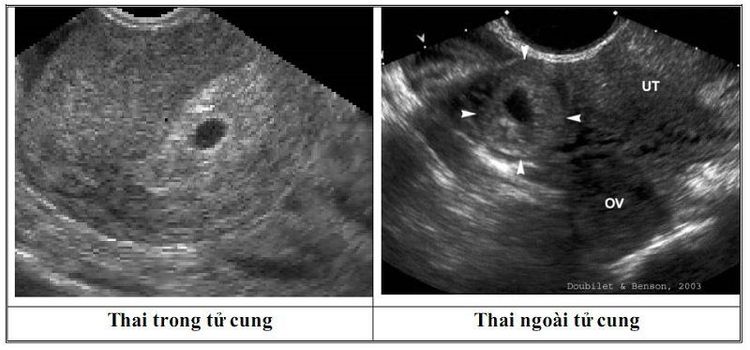

• Siêu âm: Trong chẩn đoán thai ngoài tử cung, bác sĩ có thể chỉ định siêu âm bụng và/hoặc siêu âm đầu dò âm đạo. Siêu âm đầu dò âm đạo có nhiều ưu điểm nổi bật hơn siêu âm bụng thông thường, trong đó độ chính xác và độ nhạy cao hơn. Một đầu dò nhỏ dài được đưa vào âm đạo sẽ cho phép định vị được vị trí làm tổ của thai. Các hình ảnh khảo sát tử cung, buồng trứng và vòi tử cung thu được chi tiết hơn. Siêu âm đường bụng thường được dùng xác nhận việc có thai hoặc đánh giá tình trạng chảy máu trong ổ bụng, hay phân biệt với các nguyên nhân gây đau bụng cấp tính khác như viêm ruột thừa, viêm phần phụ, ...

Thai ngoài tử cung chẩn đoán qua siêu âm